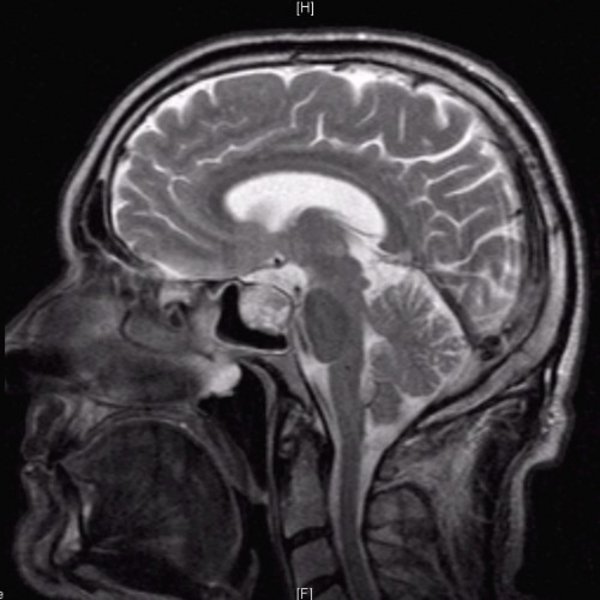

Hypophysenadenom T2 sagittal